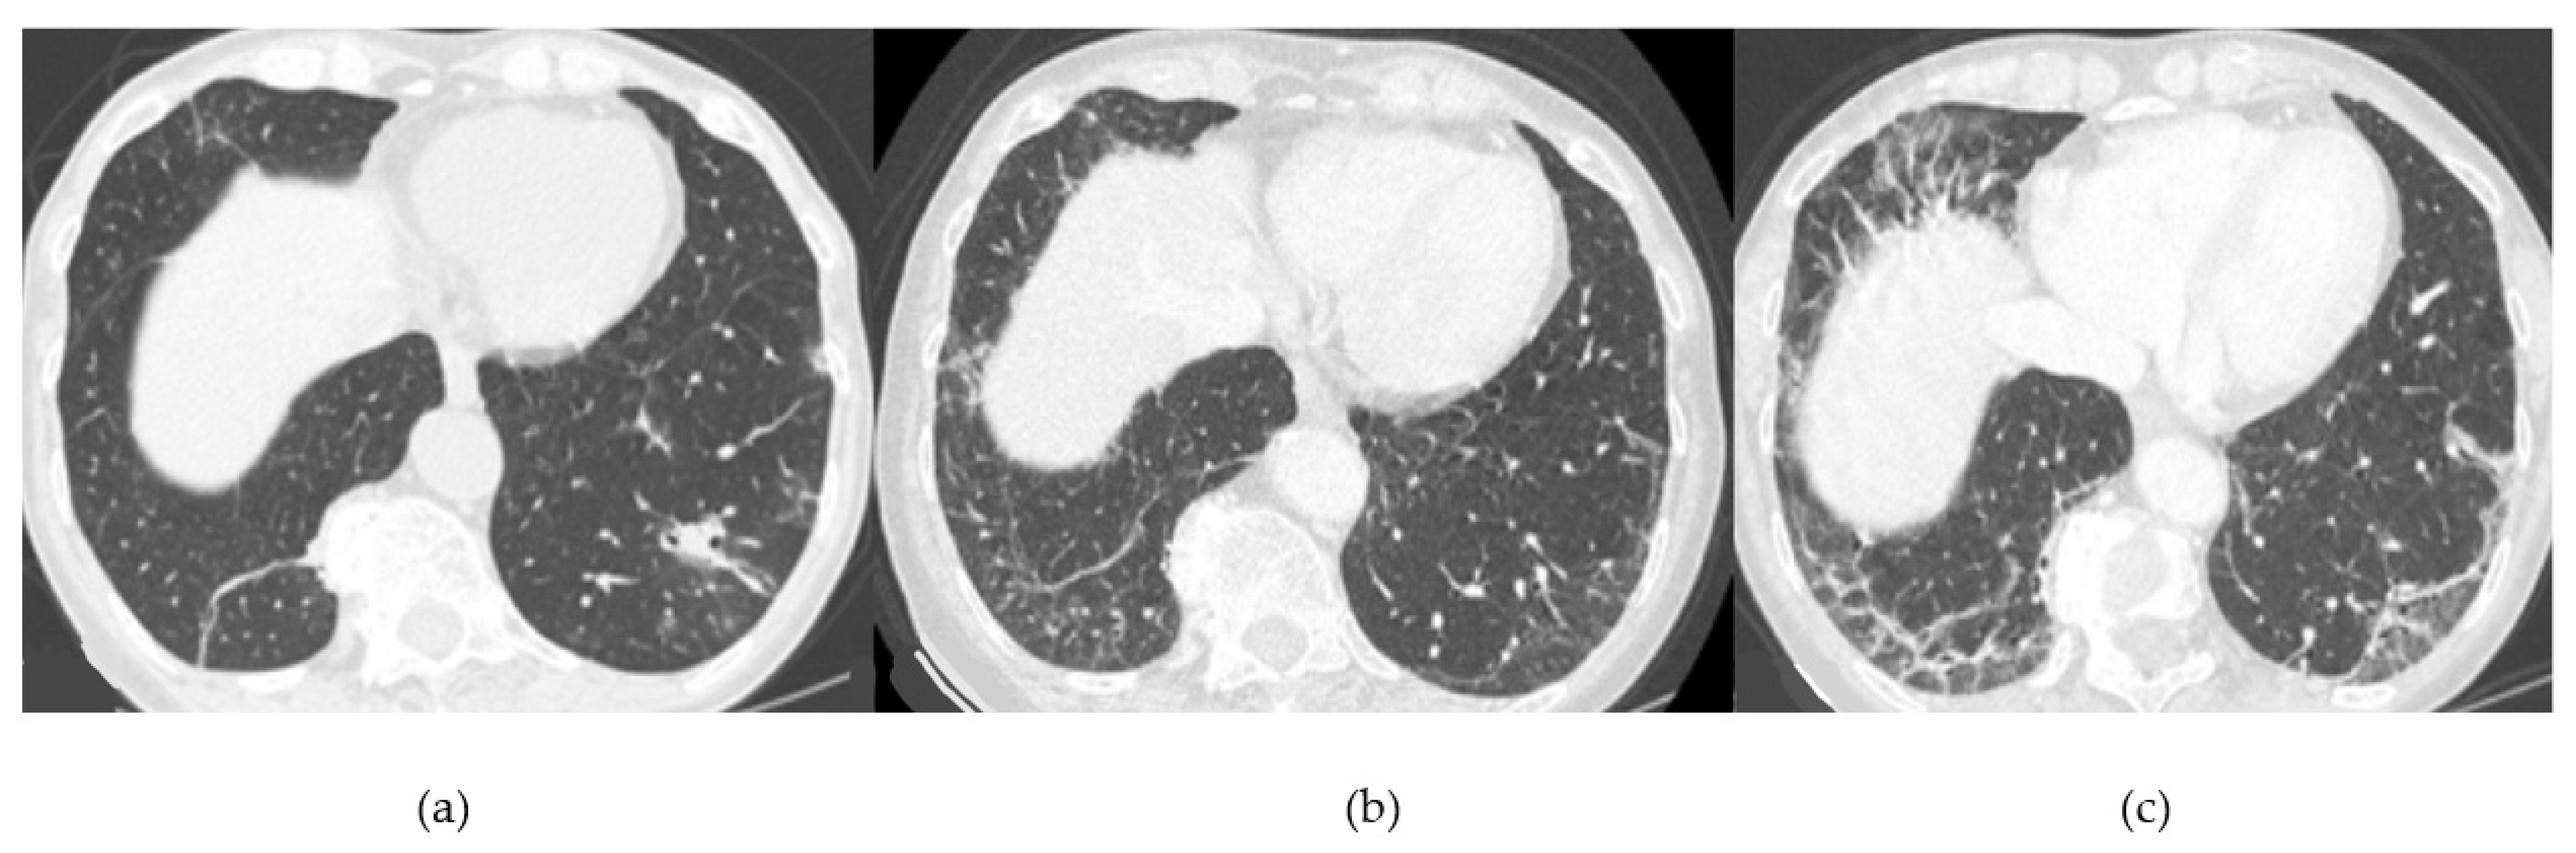

- Chronic progressive fibrosing ILD (reticulation and honeycombing with minimal GGOs on HRCT scans, related to fibrotic NSIP or UIP) [43];

| Lesions | GGO, reticulations, consolidations | consolidations, GGOs | |

| Distribution | Homogeneous; lower lung lobes, along bronchovascular bundles and lung periphery; loss of volume of lower lobes | Patchy; peripheral lower lobes or along the bronchovascular bundles | |

| CT pattern | NSIP OP NSIP-OP UIP DAD-unclassifiable | 50% 20% 25% 10% +/− | 20% 50% 25% <5% ++ |